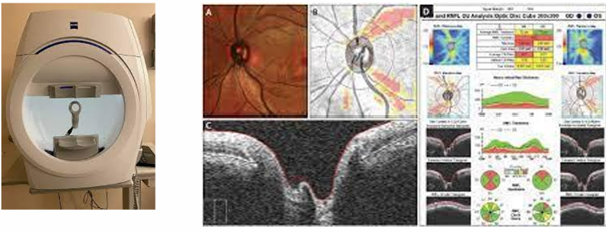

• Investigation of Primary Open Angle Glaucoma (POAG)

Visual field assessment

Slit lamp examination:

-Optic nerve head assessment

Anterior chamber assessment (Van Hericks, Gonioscopy)

• Check the IOP: Goldmann Applanation Tonometry/ Perkins

• Fundus imaging

• OCT (Anterior OCT and Optic Nerve Head OCT)